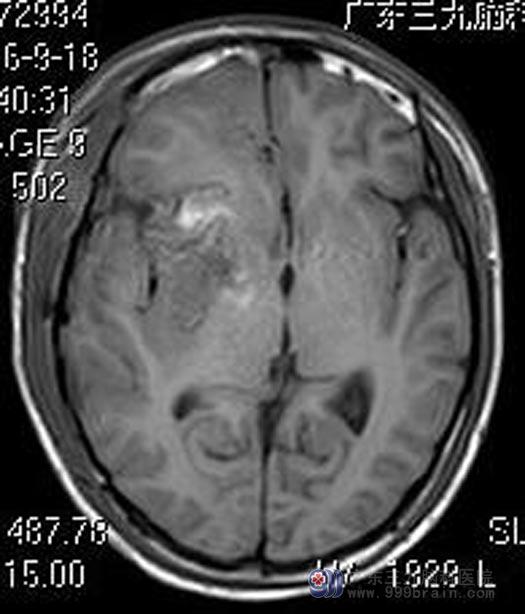

小杰今年18岁,一周前出现头痛,伴间断呕吐,当地医院头颅CT检查提示:右侧颞叶基底节区出血。广东三九脑科医院头颅MR检查提示:右侧基底节区为主占位性病变,结合SWI(磁敏感加权成像)检查考虑巨大海绵状血管瘤伴出血。

经综合神经外科鲁明主任详细讲解病情后,家属要求手术治疗。鲁明主任主刀,在全麻唤醒麻醉下行右侧额叶、基底节区巨大海绵状血管瘤切除术。术中唤醒病人,导航定位,见侧裂大脑中动脉分支,进入深度约3.0cm见黄色异常脑组织,造瘘见内含陈旧性暗红色血块,血块中夹杂灰色血管网状异常血管团,血供丰富,与周围脑组织间有一层淡黄色稀烂样组织,镜下全切除异常组织,患者语言、肢体功能正常。术后小杰康复很快,已满意出院。术后病理结果:海绵状血管瘤。